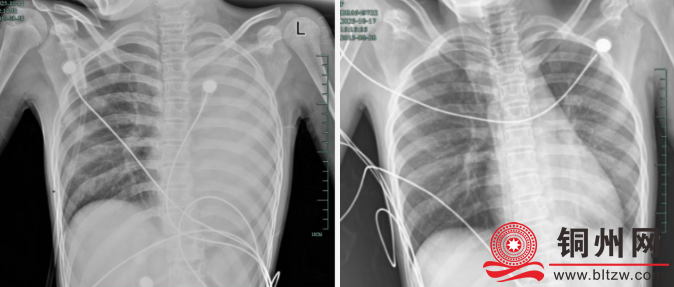

治疗前后影像对比,左肺从“白肺”到正常状态。

仅发热1天,左肺就变成了 “白肺”

据介绍,笑笑一开始只是轻微咳嗽,发热到38℃,检查提示肺炎、肺不张,转诊到浙大四院儿科时,病情已经急剧恶化,出现呼吸急促、胸闷胸痛,体温38.5℃,只能靠5L/min的面罩吸氧维持血氧,胸片显示左肺已完全呈 “白肺” 改变,肺部炎症进展迅猛。